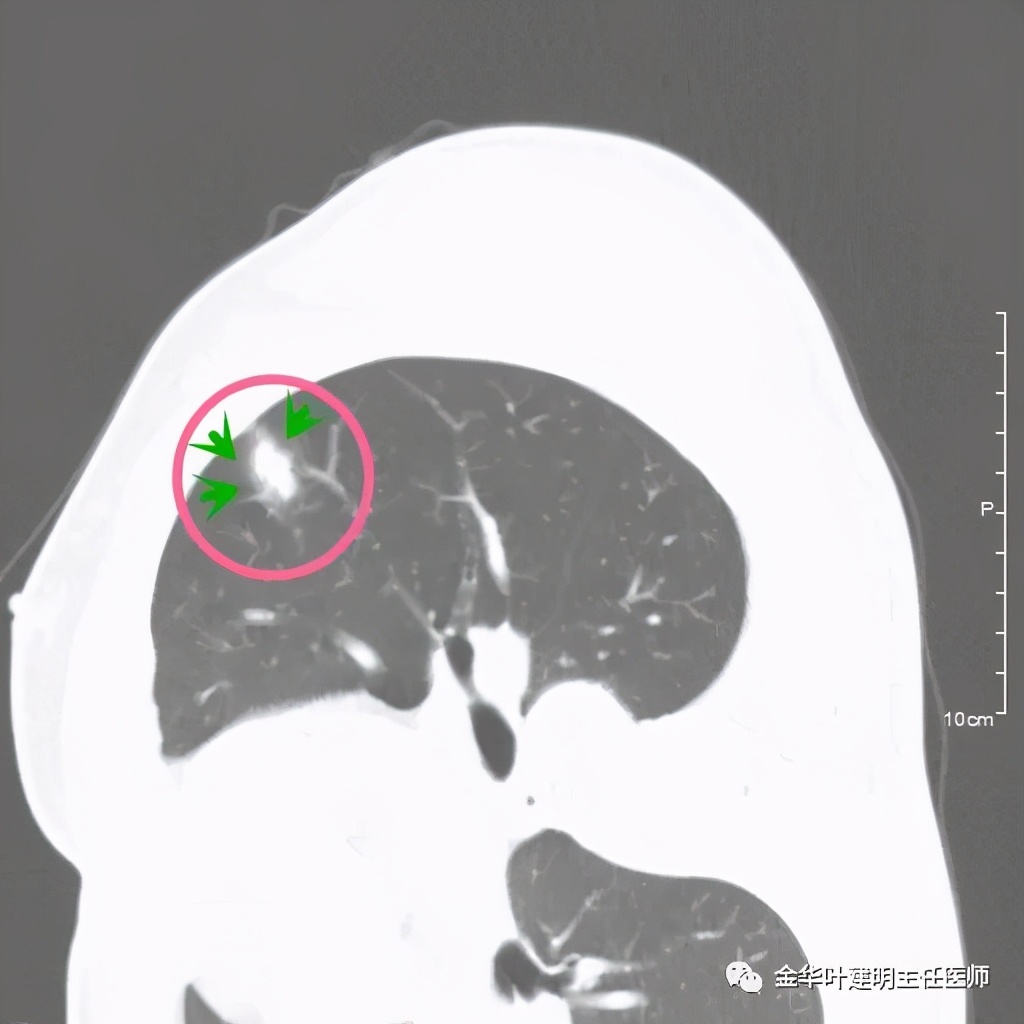

医生考虑炎性可能性大,予以头孢美唑抗炎治疗10来天,之后约一个月后复查了靶扫描,图像如下:

实性部分我看是有所缩小改善的,边上磨玻璃样的晕征更加明显了点

上图示病灶边缘向内凹陷,同时仍伴晕征

上图红色箭头示仍有血管进入,但蓝色箭头示边缘内凹,绿色示仍有晕征

上图红色箭头示血管进入病灶